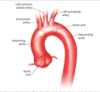

Q

Identify all arteries of aortic arch

A